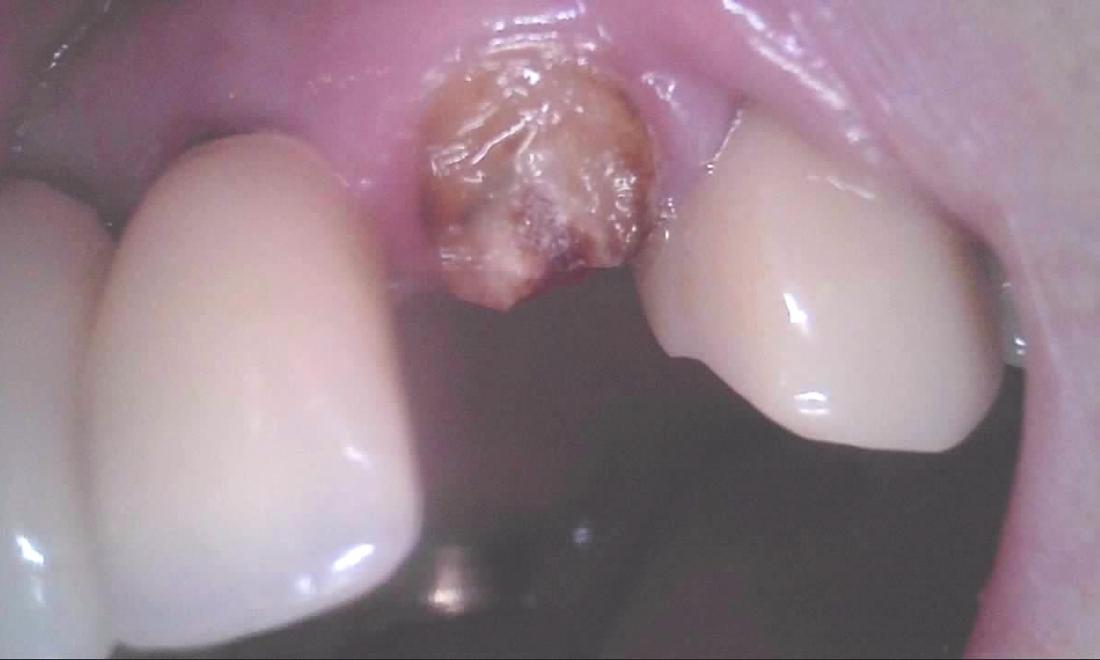

Here is an example of a tooth that had broken off at the gumline.  While people often think that every broken tooth must be pulled, in this case, we were able to do a root canal, followed by a cast post and core, and then cement a crown over the broken tooth.  This photo of the crown was taken seconds after it was cemented.  Root canals, posts, and crowns have been done for a very long time with a very good success rate, so saving teeth is always our first goal whenever possible.  We expect this tooth to have years and years of continued service.